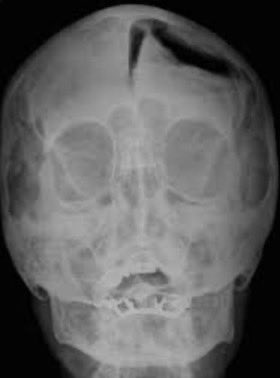

بدأت رغبتها في دخول هذا المجال الصعب لما توفى ابوها الله يرحمه بسبب حادث انكسرت فيه جمجمته وماكان في احد يقدر يساعده لضعف التقنيات والخ ذاك الوقت ، هذي صوره تقريبيه تشرح اللي صار له